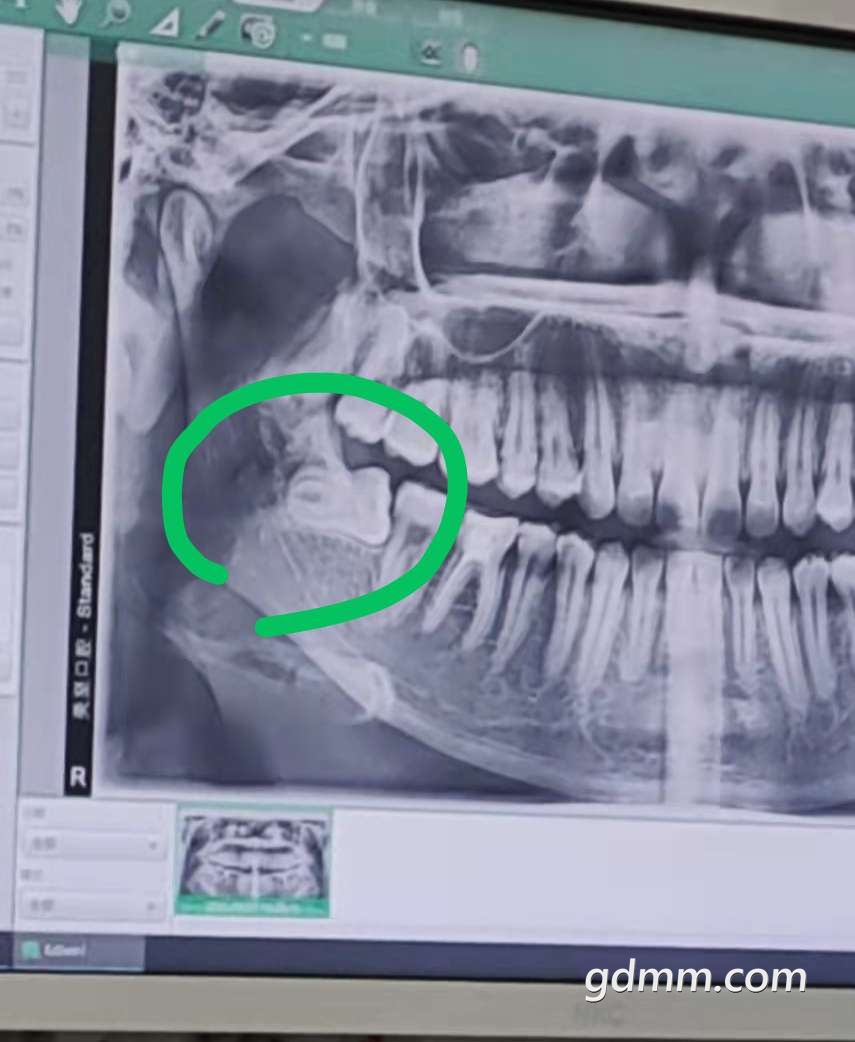

[民生百态] 拔智齿的收费范围是多少?家人最近拔智齿医生竟然收取3000+,是不是被坑了?

家人最近拔智齿,医生竟然收取3000+,而且还没包含检查费、药费……医生的说辞:牙根太弯太深,手术难度大、耗时长,费用相对高。从早上九点到下午五点才弄好。

是不是被坑了?